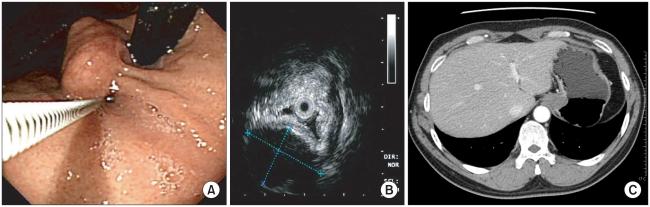

A laparoscopic wedge resection for a submucosal tumor, which is close to the gastroesophageal junction, is technically challenging. This can be a dilemma to both patients and surgeons when the tumor margin involves the gastroesophageal junction because a wedge resection in this situation might result in a deformity of the gastroesophageal junction or an injury to the lower esophageal sphincter, which ultimately results in lifelong gastroesophageal reflux disease. The patient was a 42 year-old male, whose preoperative endoscopic ultrasonographic finding did not rule out a gastrointestinal stromal tumor. He underwent a laparoscopic gastric wedge resection and prophylactic anterior partial fundoplication (Dor) and was discharged from hospital on the fifth postoperative day without any complications. There were no symptoms of reflux 5 months after surgery. A laparoscopic wedge resection and prophylactic anti-reflux surgery might be a good surgical option for a submucosal tumor at the gastroesophageal junction.

胃食管结合部黏膜下肿瘤行腹腔镜楔形切除术具有一定难度。当肿瘤边缘累及胃食管结合部时,患者和外科医生可能会陷入两难的境地,因为在这种情况下行楔形切除术可能会导致胃食管结合部变形或损伤下食管括约肌,最终导致终身胃食管反流病。该患者为 42 岁男性,术前内镜超声检查结果不能排除胃肠道间质瘤。患者接受了腹腔镜胃楔形切除术和预防性前部分胃底折叠术(Dor),术后第 5 天出院,无任何并发症。术后 5 个月无反流症状。对于胃食管结合部黏膜下肿瘤,腹腔镜楔形切除术和预防性抗反流手术可能是一种较好的手术选择。